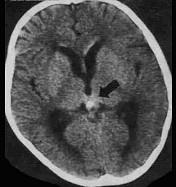

关于松果体区生殖细胞瘤(如图所示)临床表现叙述错误的是()A.共济失调B.听力障碍C.尿崩症D.Parinaud综合征E.性发育迟缓

问题 关于松果体区生殖细胞瘤(如图所示)临床表现叙述错误的是()

选项 A.共济失调 B.听力障碍 C.尿崩症 D.Parinaud综合征 E.性发育迟缓

答案 E